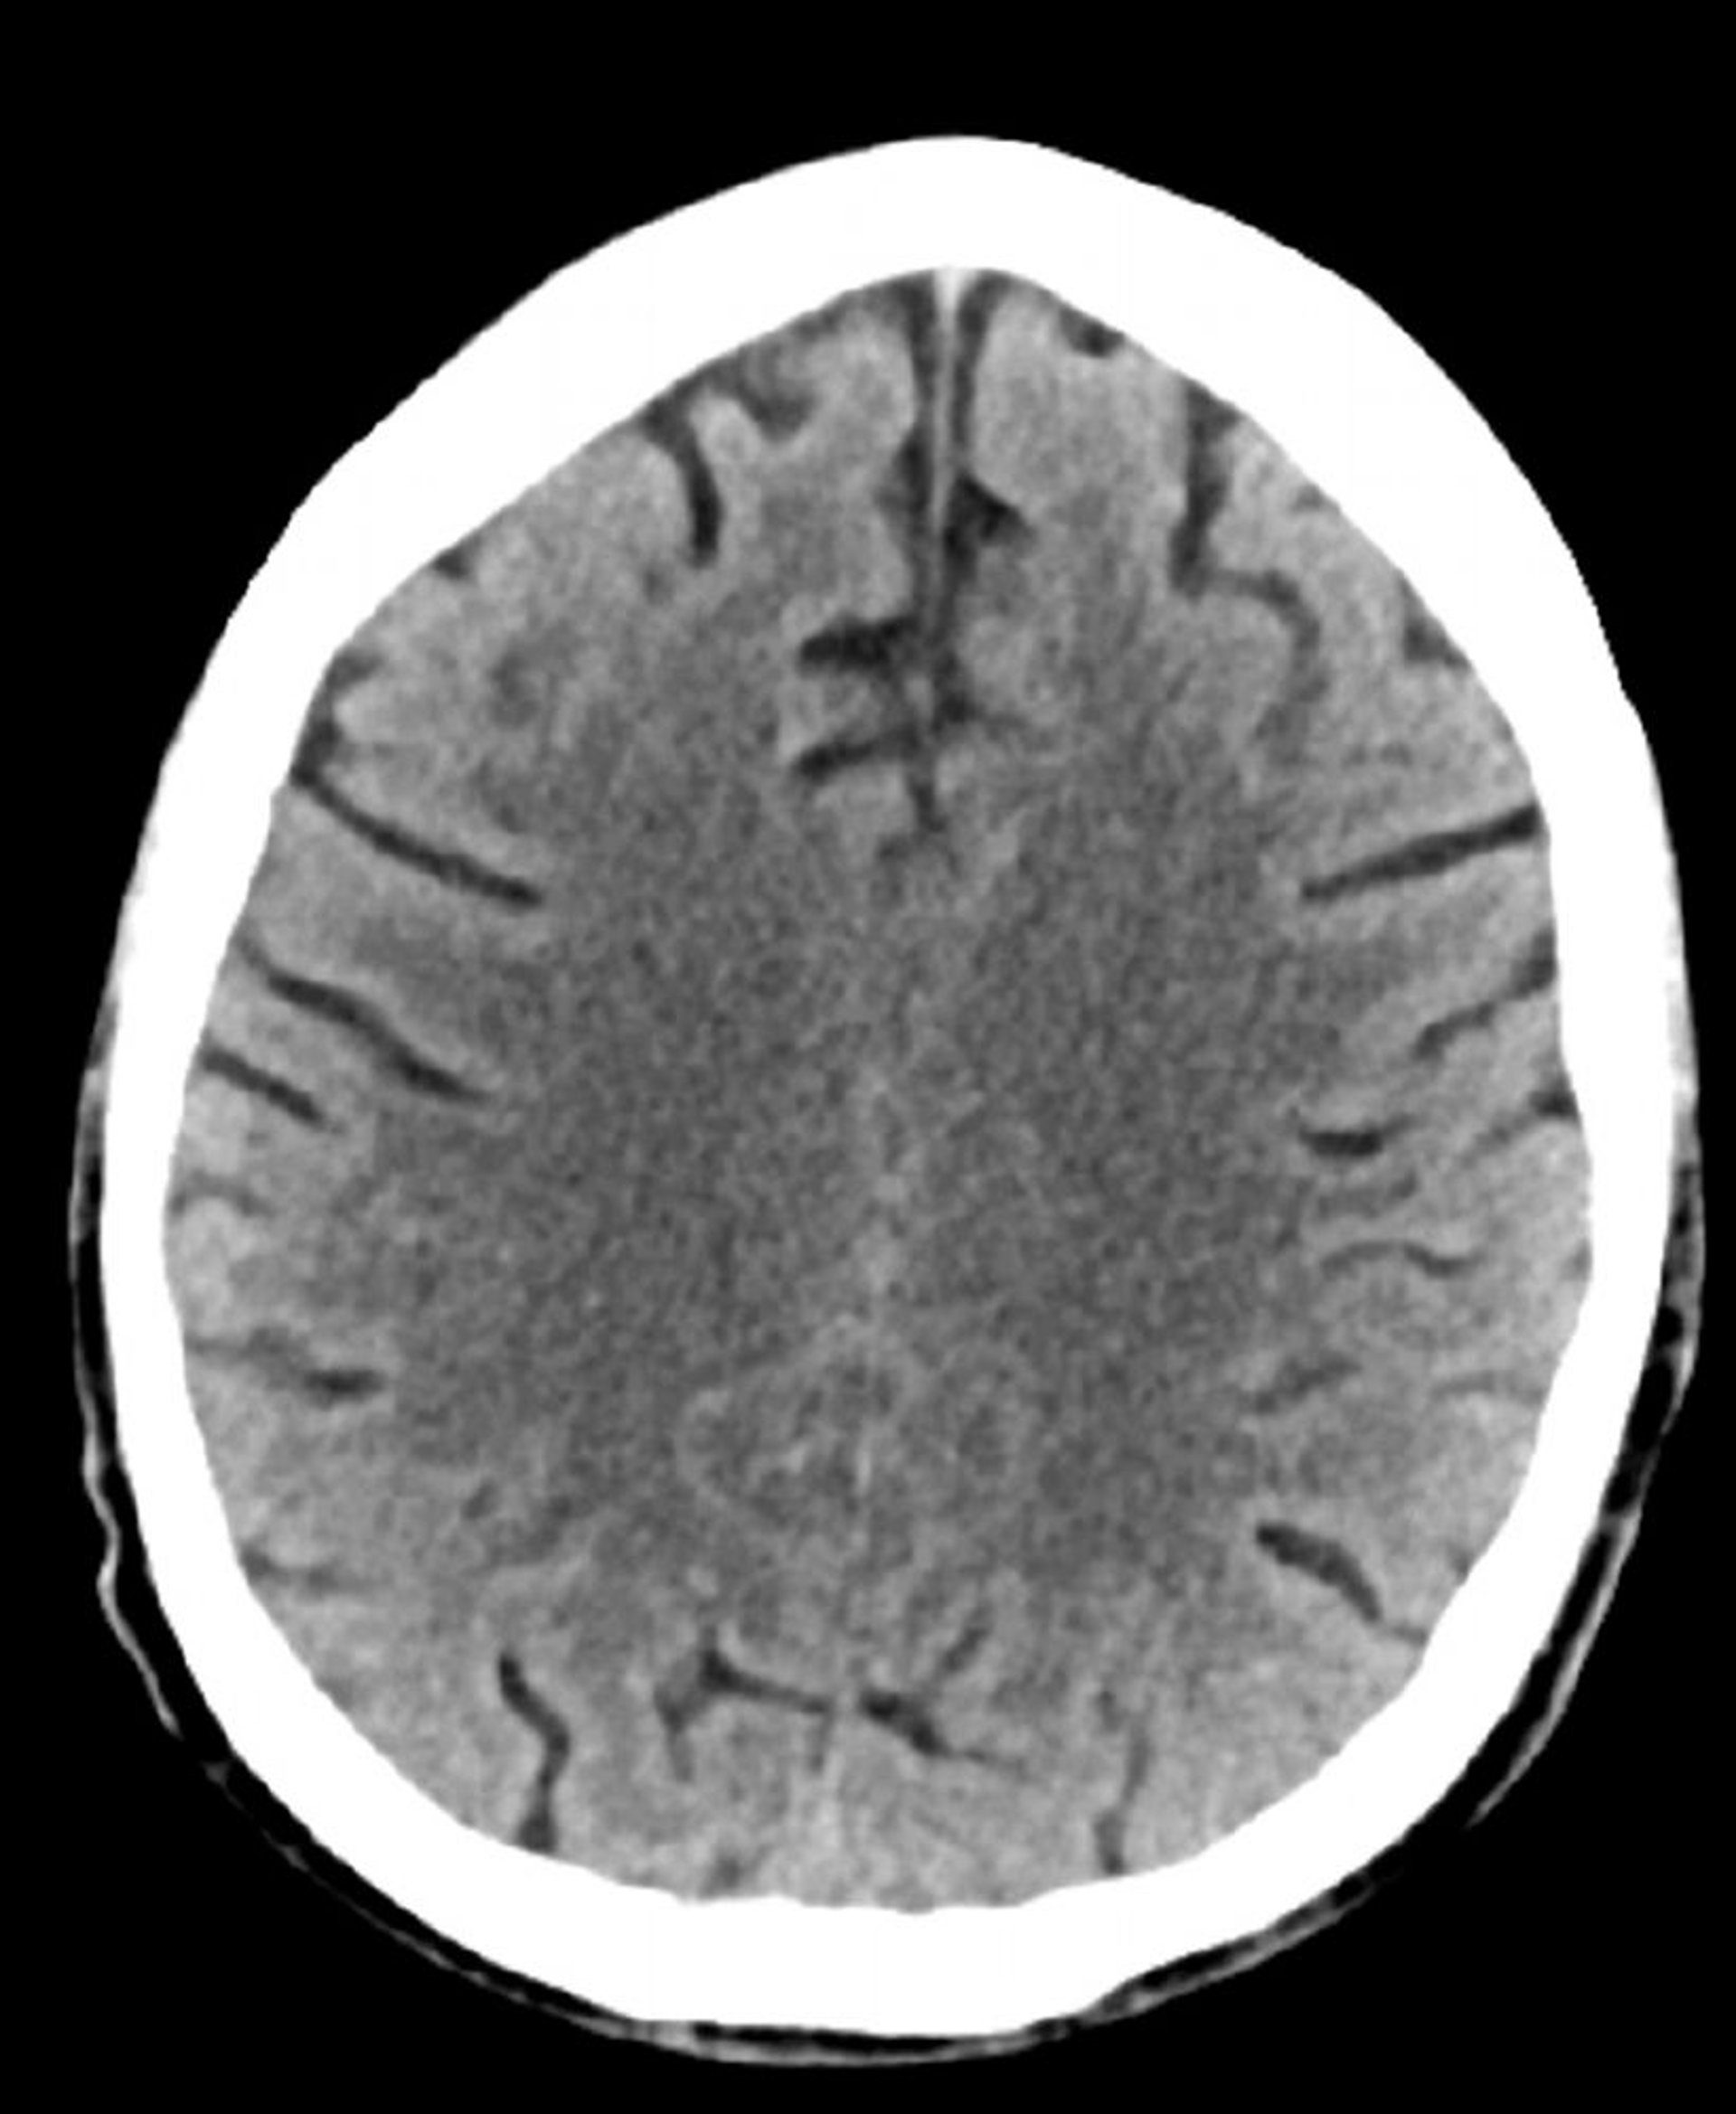

正常な頭部CT(成人,74歳)―スライド2

これは74歳成人の正常な頭部CT画像である。30歳の正常な頭部CT画像と比較すると,脳溝がより大きくなっている。これらの所見はこの年齢層では正常である。